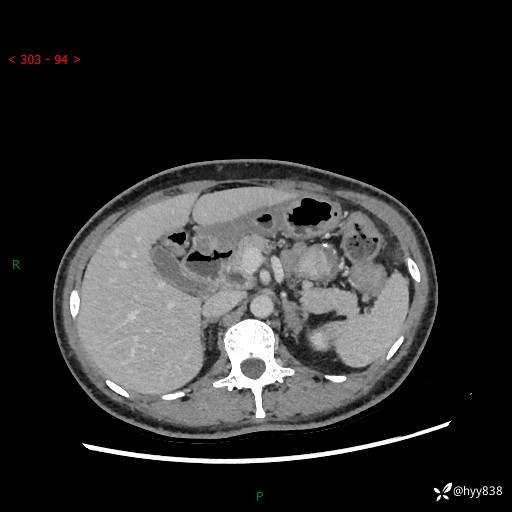

胰腺CT平扫

img